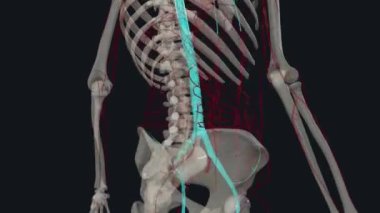

SağlıkkanİlaçkalpStetoskopTedaviHastalıkbiyolojiGöğüsorgİyileştiriyorvenanatomibelirtileriobstrüksiyonarterkapillerkasılmaAtriumGöğüs kemiğiaortKalp kriziKalp kasıGöğüs Ağrısıkalp zarınıKan damarıStentkan akımıacil tedaviKoroner artersol ventrikülSağ ventrikülkalp ilacıdiyaframdanKalp kapakçığıkardiyovasküler sistemSol atriyumPulmoner dolaşımSistemik dolaşımPulmoner arterSağ atriumsemilunar valvepulmoner venbicuspid valvepapillary musclecardiac septumcardiac wallheart catheterisationBenzer İçerikler